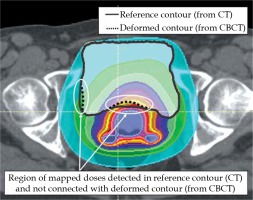

Modern BRT planning systems enable the visualization of doses on CT images by combining information of dose distribution with that of patient’s anatomy [18,19]. The quality of CT images is one of the key factors determining the complexity of dose distribution analysis in patient’s body. While CT images enable doses to be measured in most organ/regions during BRT, the quality of CBCT images reduces substantially the extent of those analyses [20]. Figure 5 shows a CBCT image made on an Acuity simulator for a volume treated with BRT. It displays the bladder (contoured with a green line), Foley’s catheter placed in the bladder (yellow line), and a three-channel Fletcher applicator (three bright points located centrally in the patient’s body). The quality of CBCT images makes it impossible to specify the exact location of the rectum and target volume and, thus, to perform a spatial analysis of doses deposited in those structures. It is, however, possible to analyze dose distribution in the bladder.